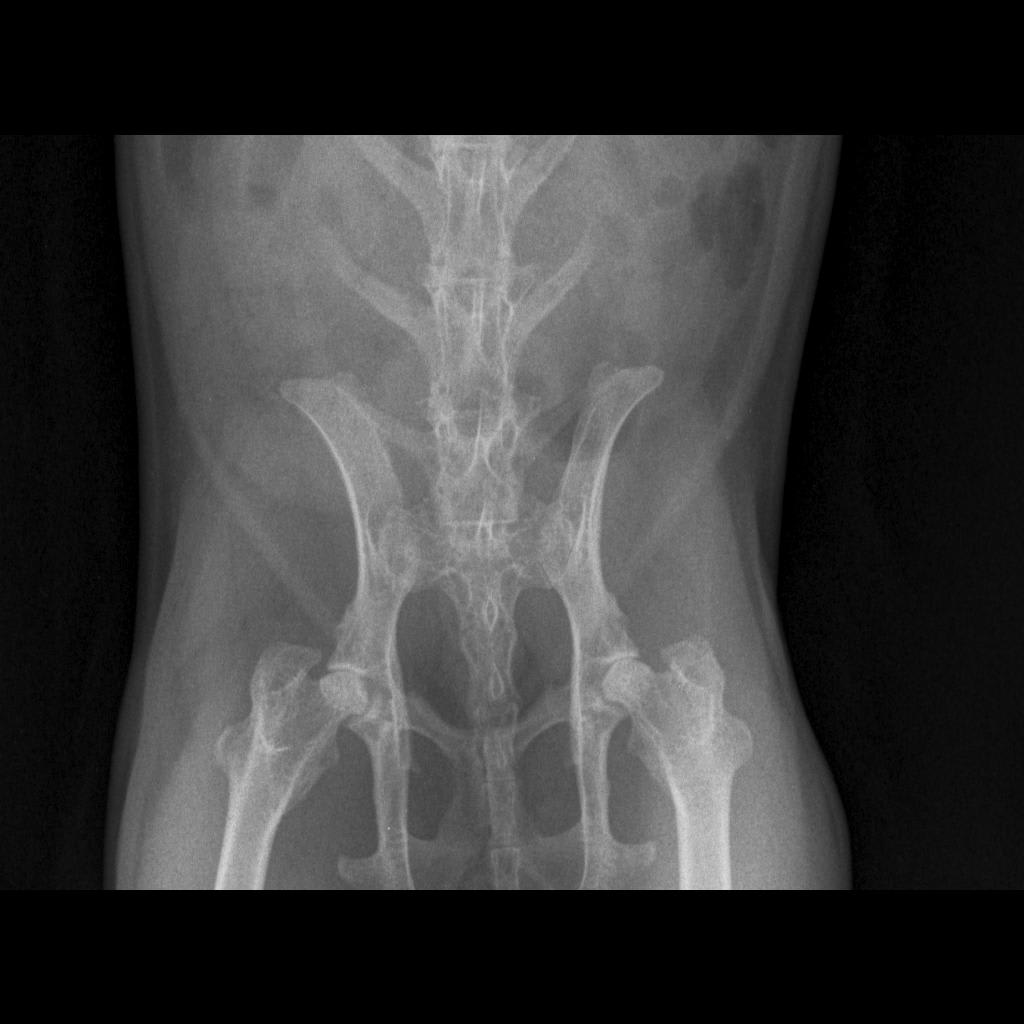

Got suggested therapy with meloxicam and glucosamine for my bunny's hip. There isn't a specialized glucosamine for bunnies, and my vet suggested Flexadin tablets. 1/4 of it a day for my 2kg bun. The ingredients per tablet (2 g): Glucosamine HCI 500mg; Chondroitin sulfate 400 mg; Harpagophytum procumbens (devil's claw) 150 mg; Manganese sulfate (provides 10 mg of manganese) 31.2 mg; Contains poultry flavour (vegetable origin). Is this safe? Attached x-ray and product. I appreciate your help.